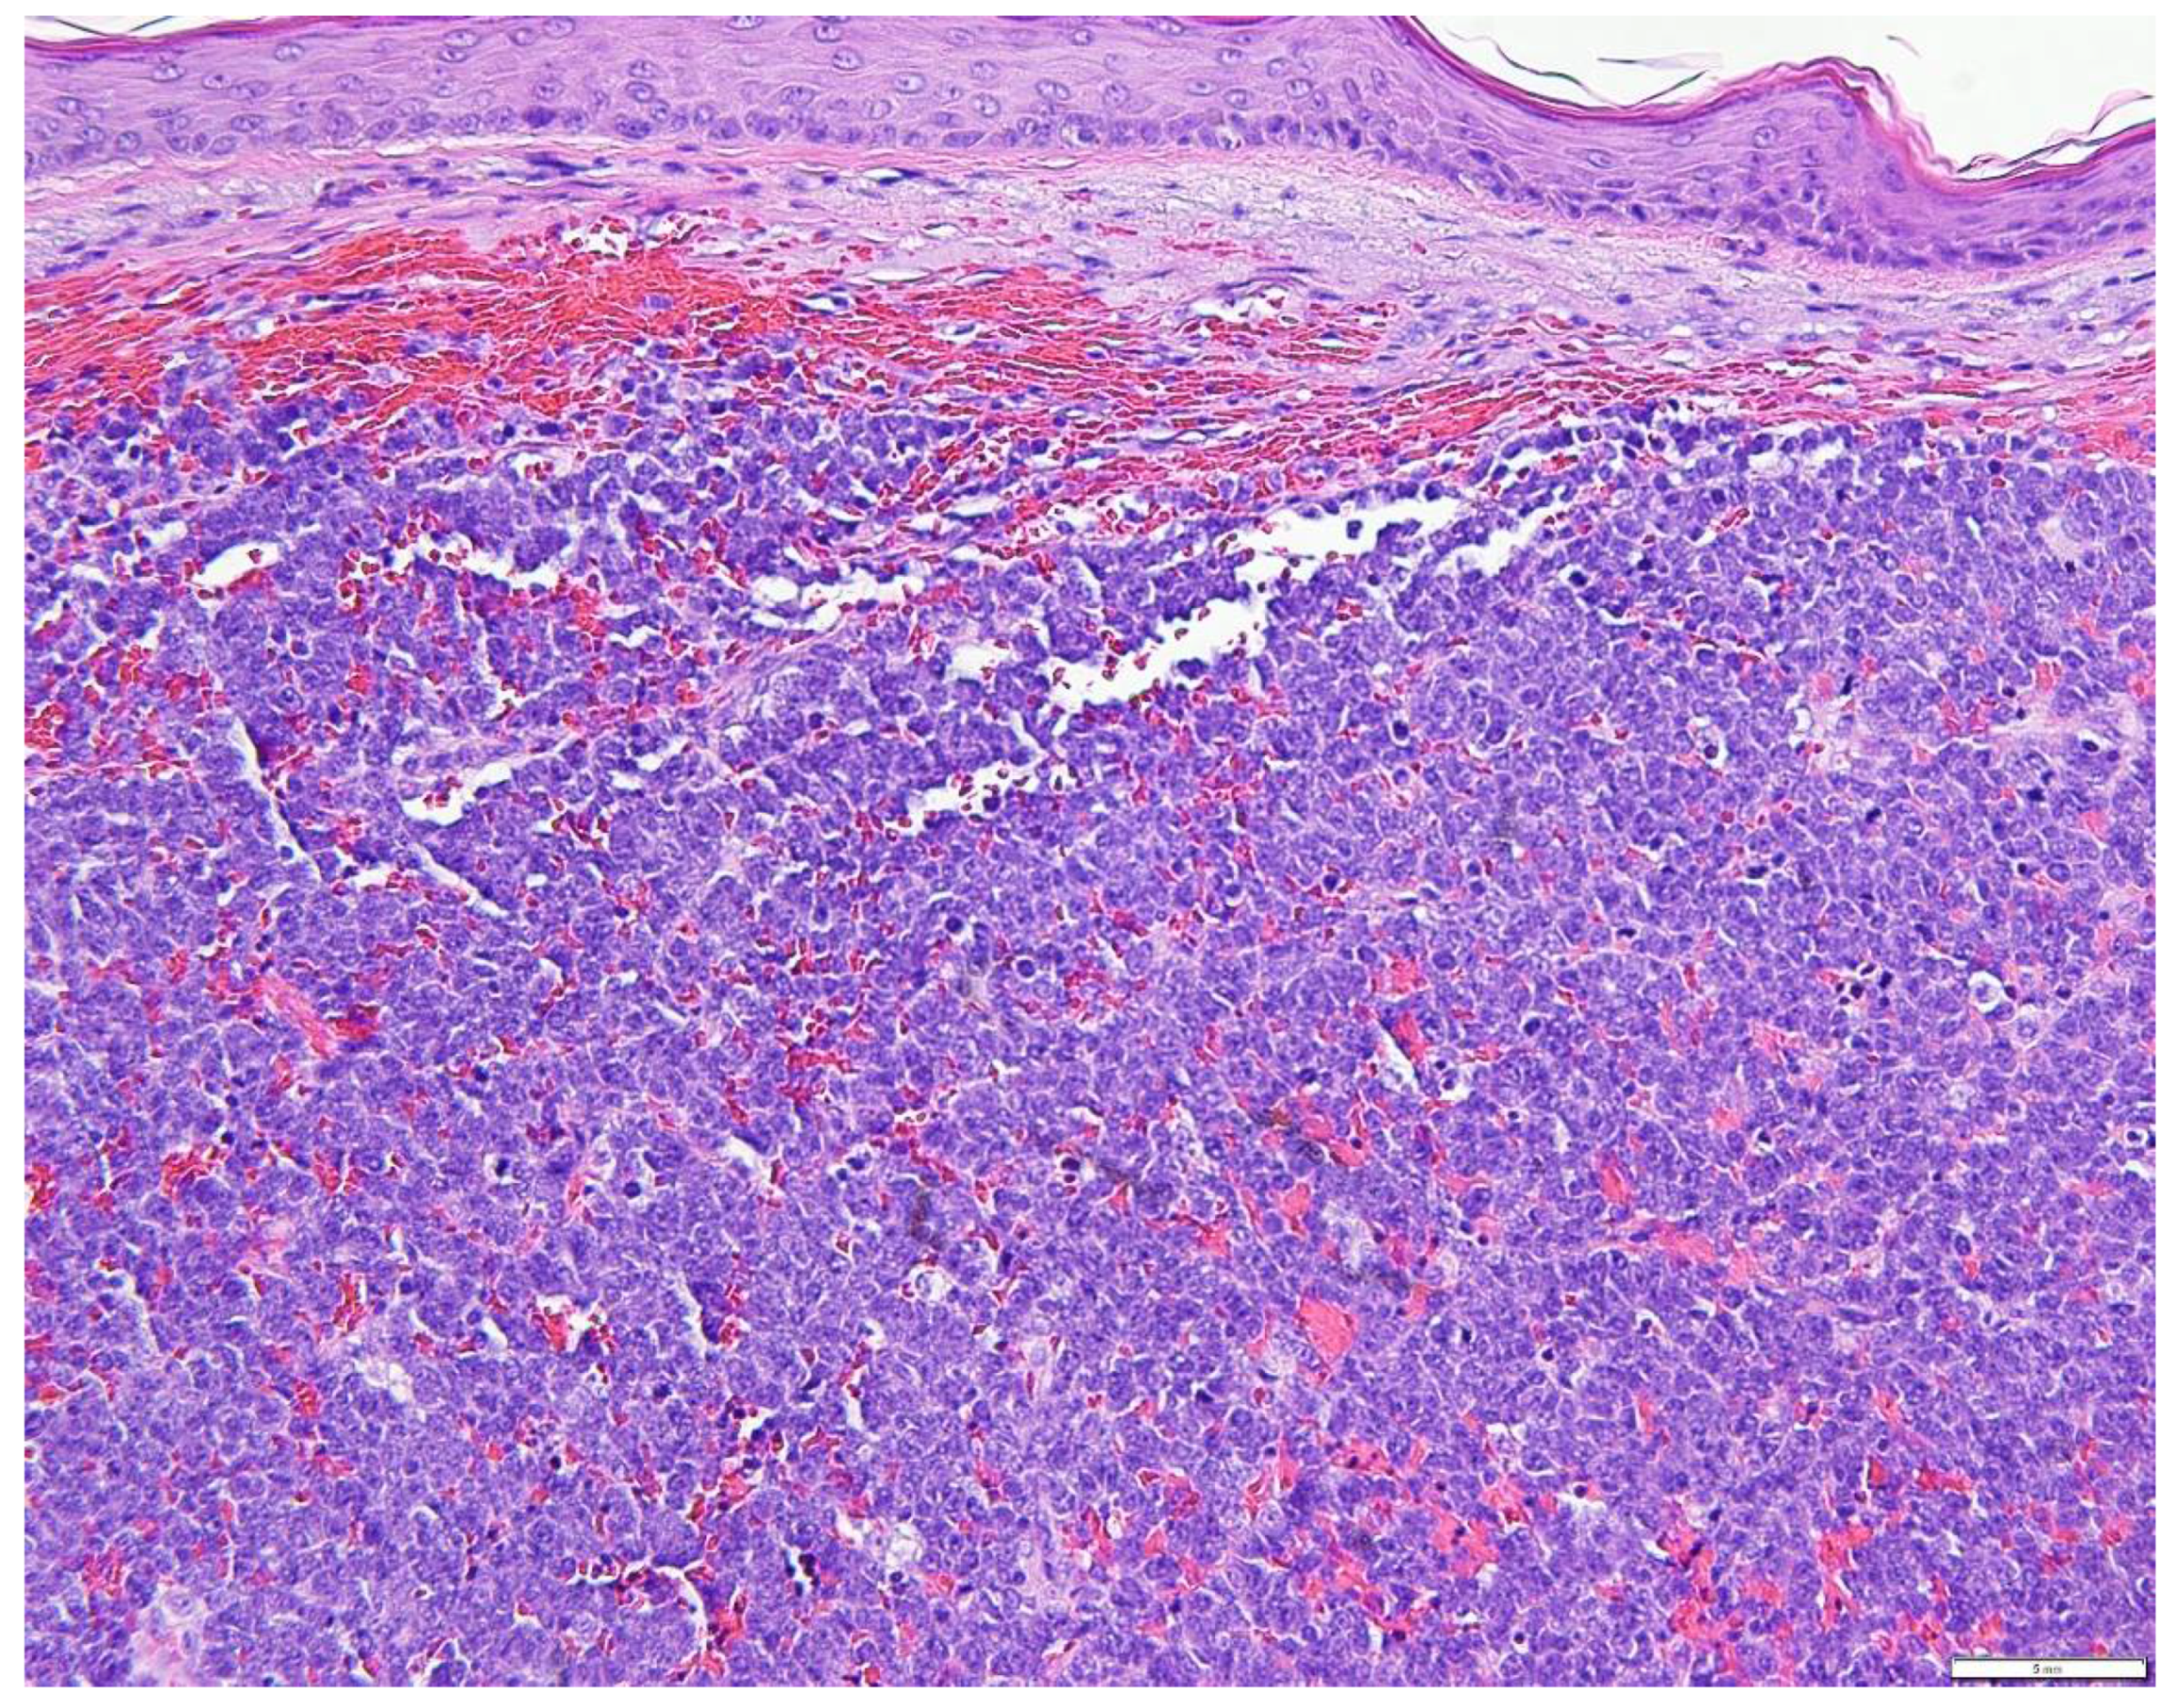

1. Introduction

5. Diagnostic Evaluation/Staging